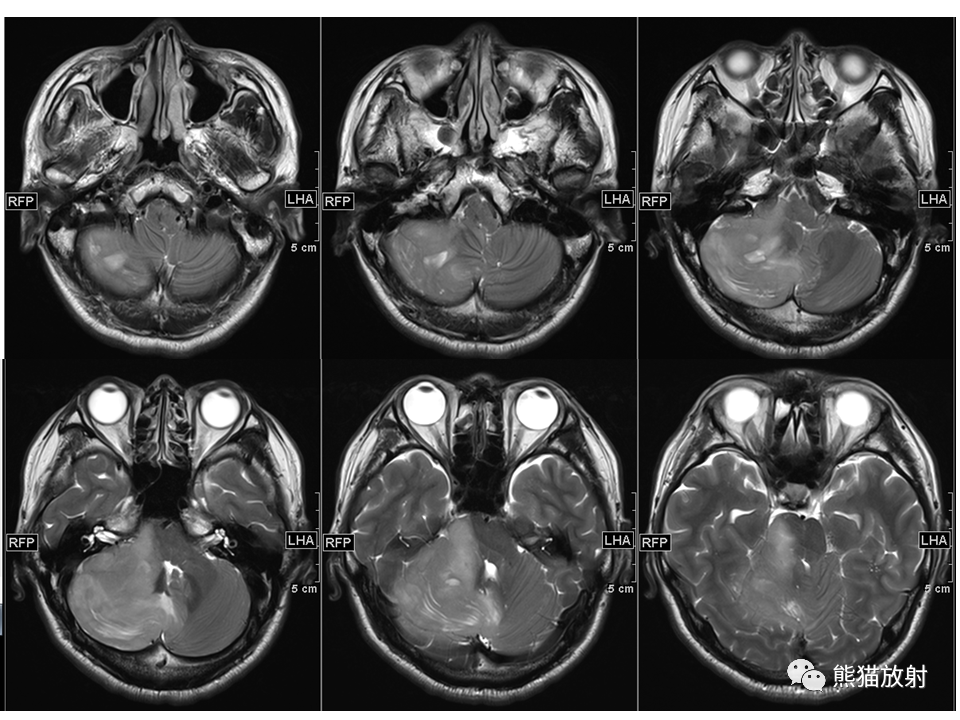

【PPT】小脑发育不良性神经节细胞瘤 VS 成人型髓母细胞瘤-4